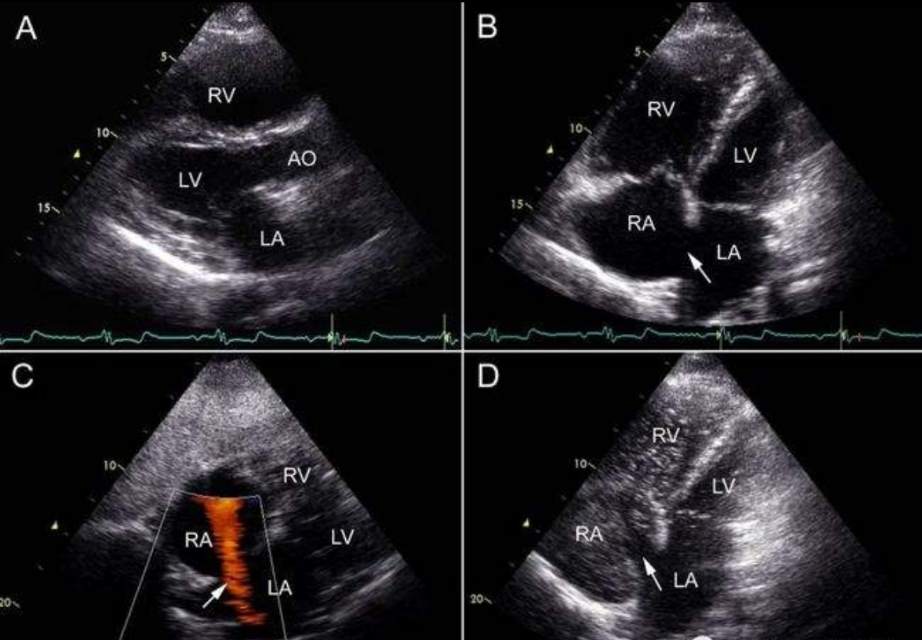

卵圆孔是胎儿发育所必需的一条生命通道,出生后大多数人原发隔、继发隔相互贴近、粘连、融合形成永久性房间隔(红色箭头所指处)。

若3岁以上卵圆孔未完全融合,遗留裂隙样通道,称为卵圆孔未闭(PFO)。

诊断依靠经胸/经食管超声心动图(白色箭头所指处),超声声学造影可发现潜在的卵圆孔未闭(黄色箭头所指处)。